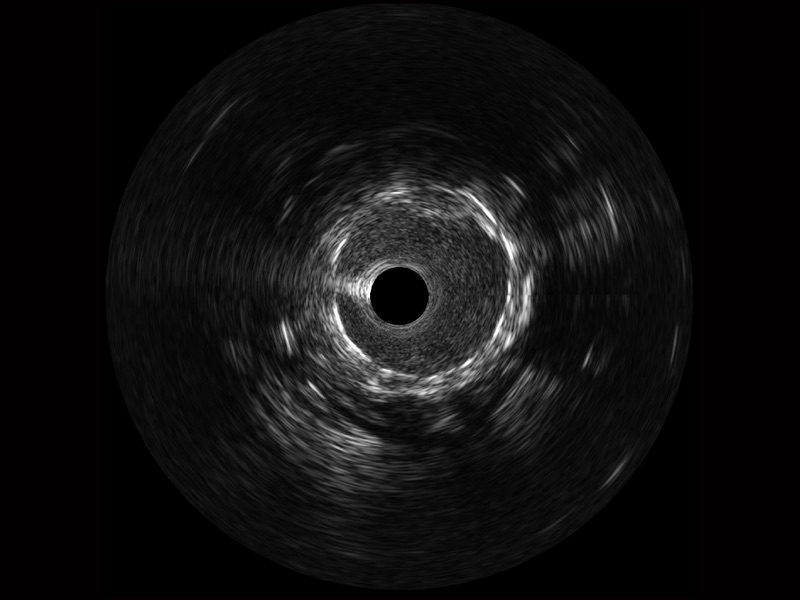

哈哈体育官网宽频IVUS图像

传统IVUS图像

对比传统IVUS导管成像,哈哈体育官网宽频IVUS图像的近场支架梁显影更细腻,远场中膜外血管仍清晰可辨,兼顾远中近,兼顾分辨力与穿透深度